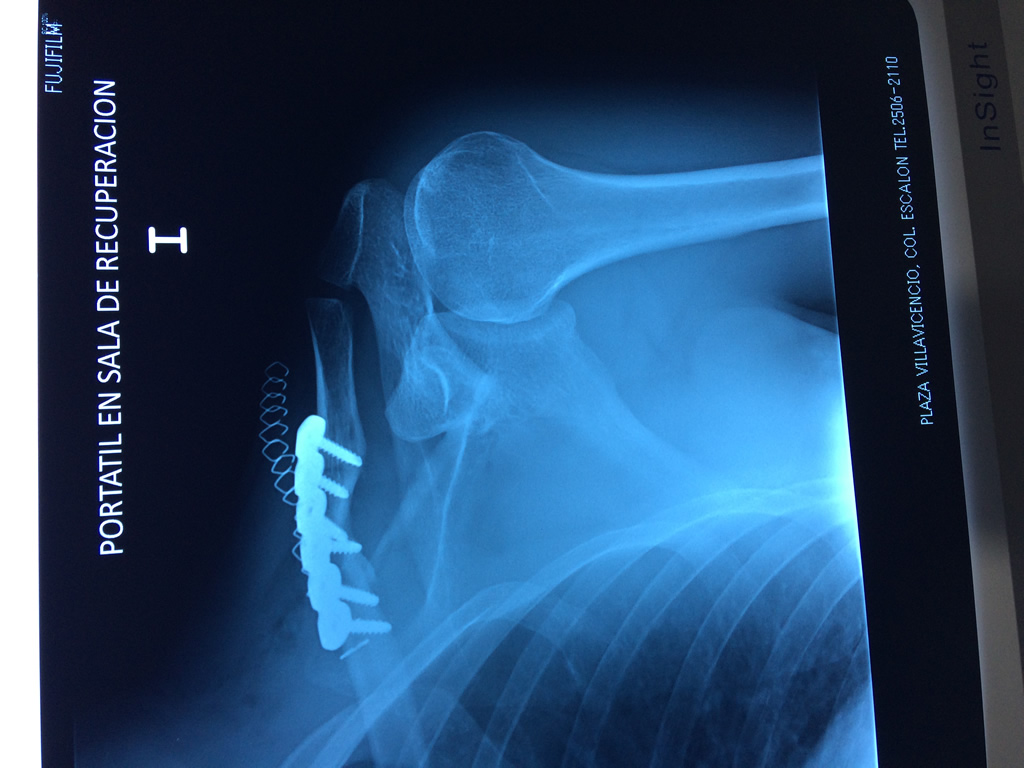

Húmero - Clavícula

La clavícula es un hueso largo, con forma de "S" itálica, situado en la parte anterosuperior del tórax. Junto con la escápula forman la cintura escapular. Se puede palpar por toda su longitud y se extiende del esternón al acromion de la escápula, siguiendo una dirección oblicua lateral y posterior.